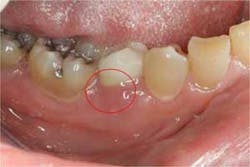

Studies have shown that cement-retained crowns have a higher incidence of peri-implant mucositis (inflammation of the peri-implant soft tissue: Figure 1) and peri-implantitis (inflammation of the peri-implant soft and hard tissue: Figures 2 and 3), likely due to the presence of excess cement following crown cementation. (4) All measures should be taken to avoid the extrusion of excess cement when cementing implant crowns. The use of a radiopaque cement is recommended to detect any excess cement radiographically immediately following cementation (Figure 4). (5) A custom cement analog also can be used to help minimize the chances of excess cement extrusion (Figures 5 and 6). (6)

Figure 1:Inflammation of the buccal soft tissue with suppuration emerging from the sulcus.